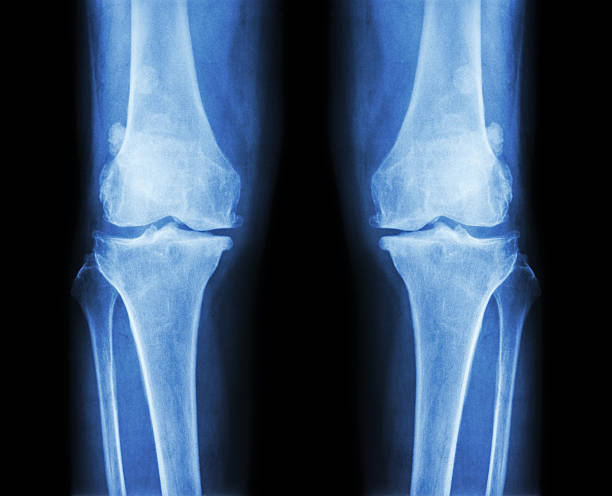

JOINT & TENDON INJURY

Common injuries treated include tendon tears, degenerative joint disease, sports injuries, plantar facciitis, and pain to shoulders, back and knees.